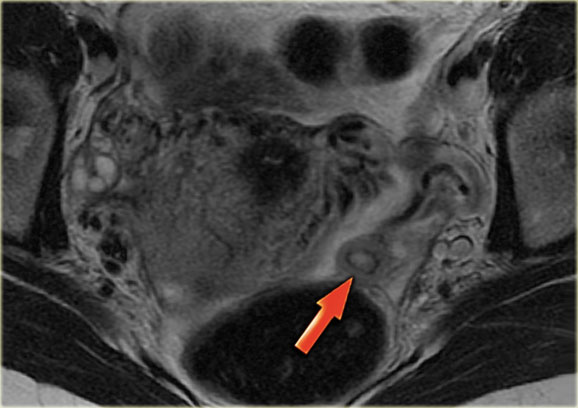

Corpus luteum cyst at MRI: an axial T2-weighted image demonstrating an involuting corpus luteum cyst (arrow).

This is a normal finding.

The right ovary is also normal.